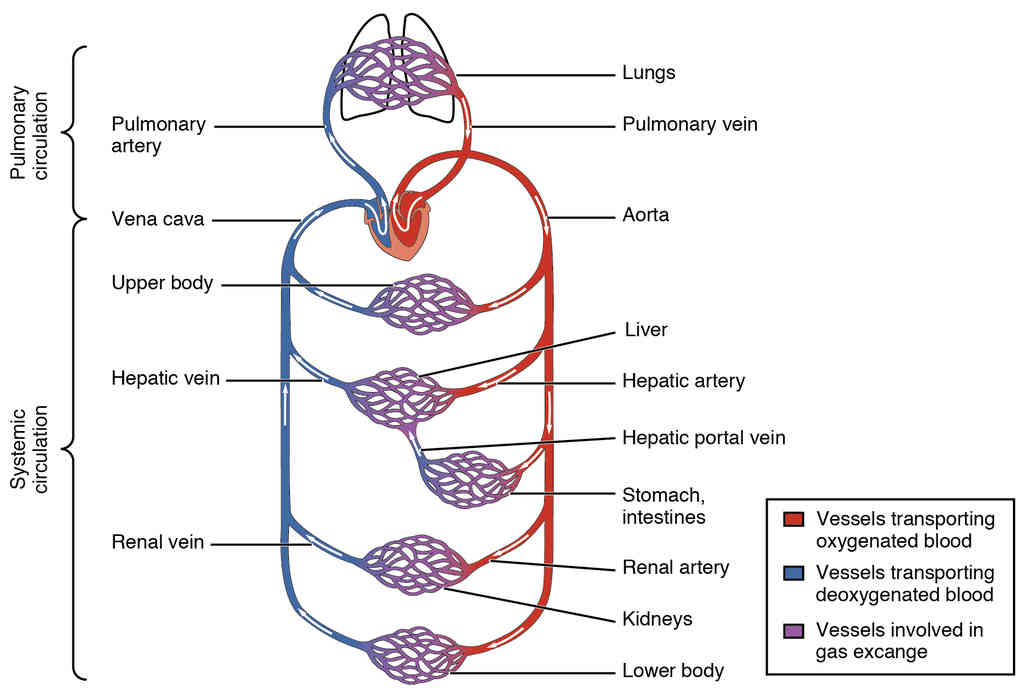

This page is under construction. For now, it is just a resource of the images found in the OpenStax Anatomy and Physiology Handbook. It wil slowly change into a revision tool. Each slide has a number. Use this to refer to the slide. When completed, it will have an unlabelled section, with labelled slides in parallel. On the unlabelled slides, write your answer and use the labelled slide to assess yourself. Keep track by also noting the number on each slide. Improvement at each attempt is important, more so than full marks on a first attempt.